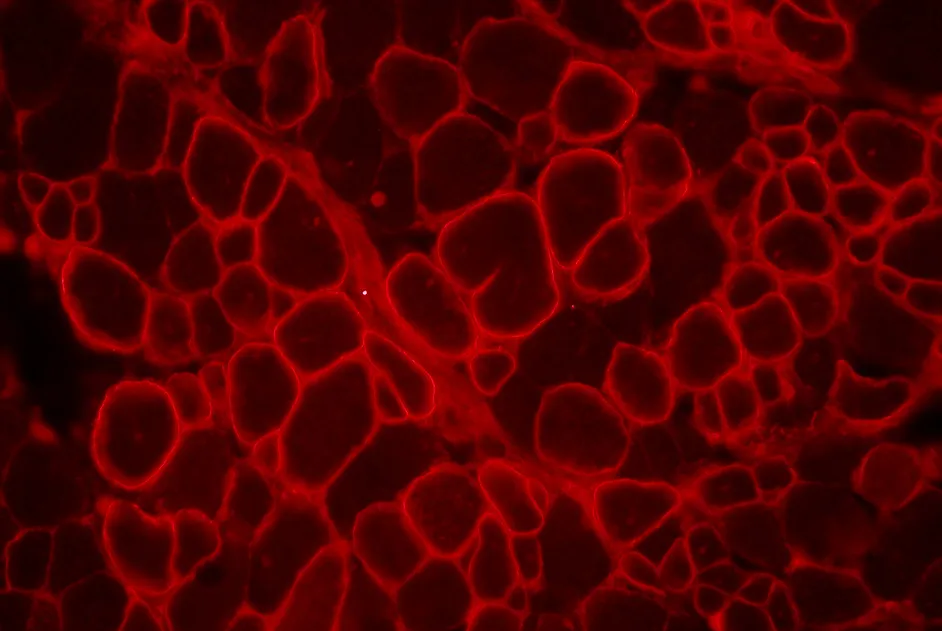

Dans l'amyotrophie spinale proximale liée à des anomalies du gène SMN1 (SMA), il n'y a pas de fabrication de protéine SMN, car celle-ci est codée par le gène SMN1. . Le gène SMN2, dont la séquence est quasi identique à celle du gène SMN1, est capable de produire la protéine SMN. La différence de SMN2 (exclusion de l'exon 7) aboutit à une importante réduction de la quantité de protéine SMN entière et fonctionnelle qu’il produit. Une piste thérapeutique consiste à augmenter la production de SMN par SMN2 à l’aide d’oligonucléotides antisens, comme le ASO-10-27, qui favorisent l’inclusion de l’exon 7 au sein du gène SMN2.

Récemment, une équipe américaine a montré une amélioration des symptômes d’une souris modèle de SMA sévère par l’injection de cet oligonucléotide antisens dans le cerveau.

Cette même équipe a publié en octobre 2011 les résultats comparant l’efficacité de l’injection de l’ASO-10-27 dans le cerveau, à l’injection systémique (c'est-à-dire dans tout le corps) dans une souris modèle de SMA sévère. L’injection systémique d’ASO-10-27 s'est montrée plus efficace sur la survie des souris modèles que l’injection dans le cerveau.

De plus, les niveaux d’IGF1 -une hormone de croissance- sont restaurés alors qu’ils sont réduits dans les souris SMA sous l’action du foie. Ces résultats suggèrent que l’expression de SMN dans les autres tissus que le cerveau est également importante pour la survie à long terme d’un modèle de SMA sévère.